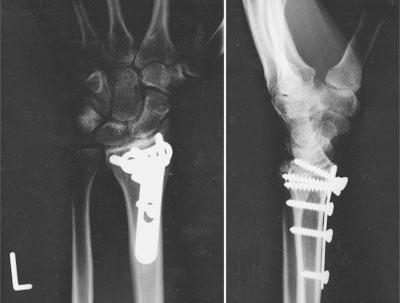

Zurück zu mir und meinem Krüppelarm. Ich konnte den Arzt nun endlich darauf festnageln ( der neue running gag), dass ich morgen früh bis spätestestens um neun das Haus der Gastlichkeit verlassen darf... denn dann wartet auch schon wieder die Arbeit... anbei noch einige Impressionen von Stahlplatten im Arm, der Charité und dem Bundespressestrand, an den mich gestern abend ein lieber Mensch entführt hat....

Nach-der-OP charit- charit-2 bsp2006_4